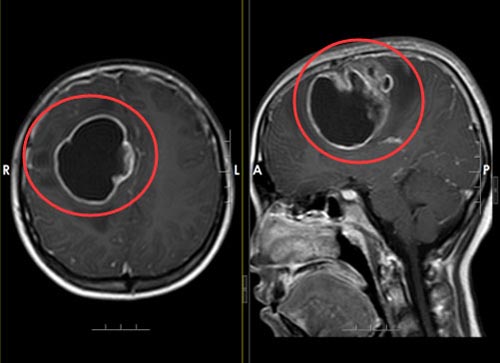

进一步头颅MR平扫+增强提示:右额叶巨大囊实性占位性病变。小丽由于剧烈头痛加上长时间的呕吐,精神状态非常差,左侧肌力IV级。鲁明副院长查房后考虑:1.右额叶占位性病变,胶质瘤?2.右侧大脑镰下疝。小丽病情严重,随时都有可能出现病情变化,肿瘤占位效应明显,有明确的手术指征,需尽快完善术前准备实施手术。

▲手术前